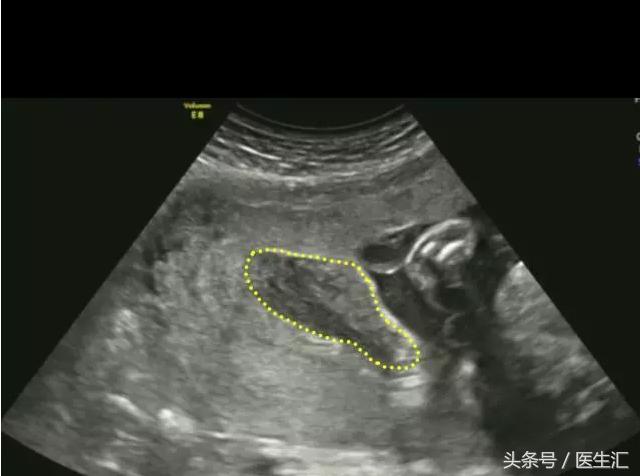

超声检查提示:宫底后壁胎盘与后壁肌层之间见混合回声区(超声表现1,见图1黄色圈内),与胎盘分界不清,范围约75mm×34mm,内回声不均匀,边缘及内部未见明显血流信号(检查要点1)。急诊剖宫产手术见胎盘80mm×50mm剥离面,占1/2(超过胎盘面积的1/3),宫腔积血约50ml,术后诊断胎盘早剥。

(图1)